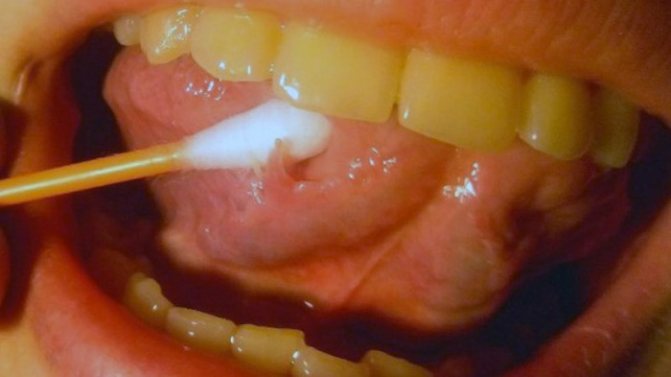

- Остроконечные кондиломы появляются, в случае, если заражение случилось сексуальным путем. Непосредственно для данных наростов свойственно объединение и формирование большой опухоли с неровной бугорчатой поверхностью.

- Остроконечные кондиломы возникают, если заражение произошло половым путем. Именно для этих наростов характерно сливание и образование большой опухоли с неровной бугристой поверхностью

Симптомы и признаки наличия кондиломы довольно тяжело спутать с другими различными заболеваниями. Остроконечные кондиломы во рту формируются в виде наростов, которые имеют светло-розовый цвет.

Во время распространения по полости рта они могут образовывать группы и проявляться в виде небольших узелков серебристого цвета. С течением времени кондиломы на языке, фото которых расположено ниже, начинают доставлять физические и психологический дискомфорт, так как во время разговора они могут быть заметны, особенно, когда формируются на языке.

Сами по себе наросты не являются причиной воспаления слизистой полости рта. Но в случаях, когда на поврежденные участки эпителия попадают бактерии, начинает появляться гной в области образования кондилом. Кроме этого они часто травмируются во время еды или разговора.

В результате начинают кровоточить и превращаются в небольшие язвы, которые хорошо видны на фото ниже. Со временем они покрываются корочкой, которая становится причиной возникновения боли и развития доброкачественных и злокачественных образований.